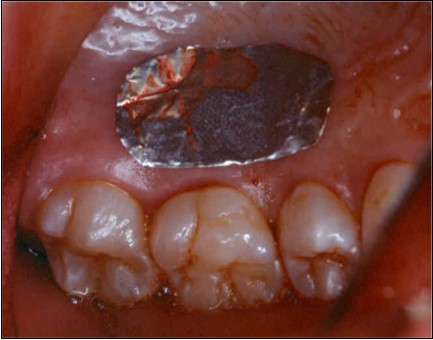

The patient under hard emotional stress that associated with bacterial plaque promoted ANUG with necrosis of alveolar bone and marginal gingival soft tissue in 31 and 41 (Figure 1). The patient was free of systemic disease and was not currently receiving any medication. Initial therapy was carried out using Er-YAG laser, to promote scaling and root planning and oral hygiene instruction. After initial therapy (Figure 2) the surgical method employed consists of the following steps as described by Langer and Langer5.

Figure 1.ANUG

ANUG